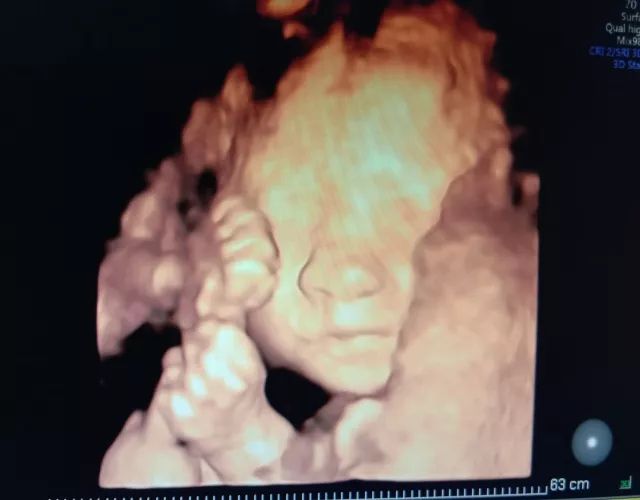

为什么孕期需要做4-5次超声检查,算不算过度医疗?

孕期长达40周,不同孕期进行超声检查有不同用途,早孕期超声用来判断胚胎着床位置是否正常,以及是否有心管搏动;12周左右行NT检查测量胎儿颈背部皮肤厚度,是为了早期发现存在染色体异常可疑的胎儿;23周系统彩超,即大排畸,是对胎儿各个系统是否存在异常,畸形等进行大范围排查;现在,我们常建议孕妇在28周做小排畸彩超,目的是动态观测胎儿的生长情况,同时对结构进行补充扫查,因为有些疾病随胎儿孕周增大慢慢表现出来,比如膈疝;在分娩之前,孕妇做最后一次彩超,为产科医生提供胎儿大小,胎位,胎盘成熟度,羊水量等数据,做好分娩准备。所以说,对孕妈妈进行的这些彩超检查都是必要的,并不是过度医疗。